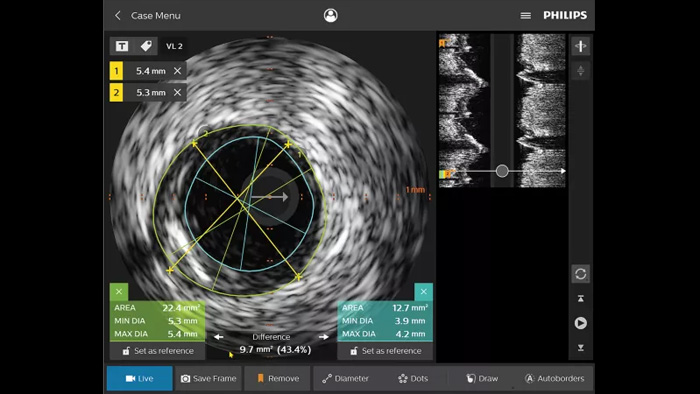

O ultrassom intravascular (IVUS) é uma tecnologia de diagnóstico por imagem baseada em cateter que permite que os médicos visualizem vasos sanguíneos de dentro para fora para ajudar na avaliação da presença e extensão de doenças. O IVUS ajuda a decidir, orientar e confirmar o tratamento intervencionista certo para cada paciente.